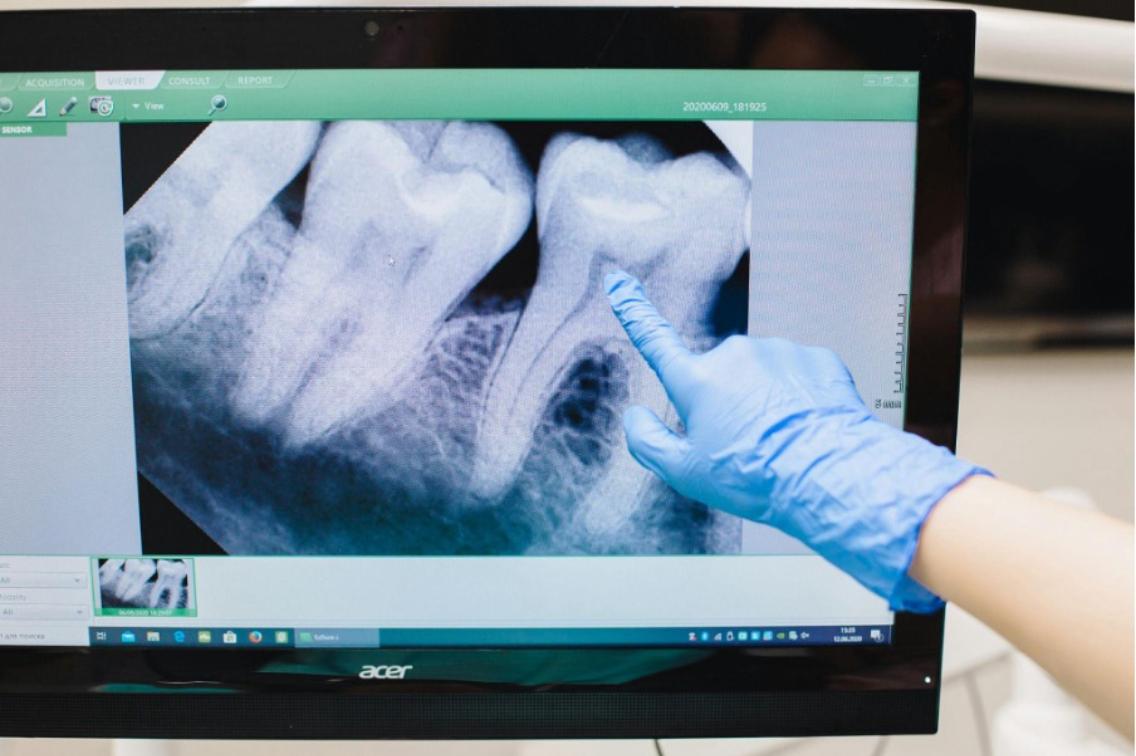

前面提到,顎骨可分為基底骨與齒槽骨。齒槽骨的功用是負責支撐、保護牙齒,並分散、承受咬合的力量,如同蓋房子的地基,是專為牙齒而生的骨頭。然而,嚴重的牙周病、長期缺牙或不合的活動假牙等問題,都可能造成齒槽骨流失。

一旦齒槽骨流失,就會影響牙齒的穩定性,若是齒槽骨流失的情況過於嚴重,可能會讓牙齒根部外露,變成敏感性牙齒,甚至造成牙齒鬆動、掉牙等問題。對於後續想做植牙的人來說,由於缺乏足夠的齒槽骨去穩固植體,就像房子缺少穩固的地基,木樁打下來去會東倒西歪的,植牙成功率將大打折扣。

杜哲彰醫師指出,根據文獻,拔牙 6 個月之後,齒槽骨的水平寬度會減少 29% ~ 63%,垂直高度減少 11% ~ 22%,其中三分之二的變化發生在拔牙後的 3 個月。這並不是告訴我們應該在拔牙當下立即植牙以防止齒槽吸收。相反地,即拔即種無法阻止骨頭吸收,且有一定風險,雖然可縮短重建時程,但不是每個人都適合。有些人必須等 4 ~ 8 週,軟組織等傷口癒合後才進行植牙,有些甚至須等待 3 個月以上,這段時間就有齒槽骨流失的風險。